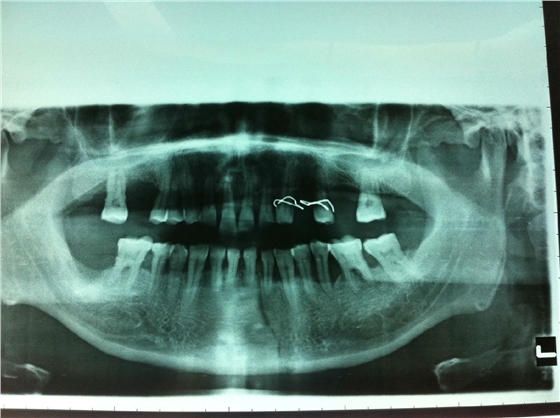

患者男性,主因左面部反復腫脹半年余,就診后行全景片檢查,發(fā)現(xiàn)下頜骨多發(fā)性囊腫,初步診斷為多發(fā)性頜骨囊腫綜合征,安排住院手術。

入院后全麻下手術治療,左側下頜骨囊腫較大,術前考慮病理性骨折可能,準備鈦釘鈦板固定,術中摘除囊腫后,發(fā)現(xiàn)下頜骨下緣骨量尚可,未給予固定。術后病理診斷為下頜骨角化囊腫,考慮到患者可能為基底細胞癌綜合征,術中切除頸部皮膚痣兩處,術后病理診斷為:皮膚痣,排除基底細胞癌綜合征?;颊哂凶髠鹊诹吖欠植胬?,綜合以上特征,最終診斷為多發(fā)性頜骨囊腫綜合征。